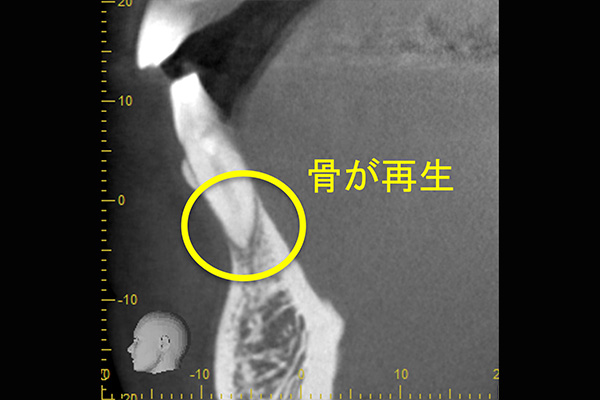

①自覚症状なし・歯肉にサイナストラクト(排膿路)あり

②初診時レントゲン解説

・歯根周囲に透過像(黒い影)あり

・遠心根根管充填:アンダー

根管治療そのものは、2回で終了し、水酸化カルシウム貼薬し経過観察(患者様希望のため)

約2か月後、根尖透過像の縮小を確認し根管充填(MTA使用)。

レントゲン解説:4根管すべてに根管充填が密にされていることを確認できる

透過像は消失し、明らかな骨形成を認める。(黒い影の消失)